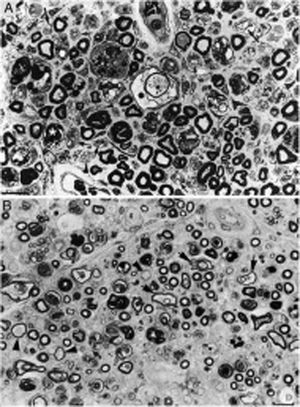

Composición de la figura 3 de Berciano et al.38 (A) y de la figura 2 de Feasby et al.37 (B), ambas correspondientes a secciones semifinas transversas de raíces raquídeas lumbares.

A)Manteniendo los recursos gráficos originales, obsérvese la presencia de numerosos macrófagos endoneurales repletos de gotitas grasa, a veces rodeando a fibras con colapso de la mielina (asteriscos blancos) o dentro de tubos neurales totalmente desestructurados. Se observan también racimos regenerativos que contienen ya axones no mielinizados (puntas de flecha) o bien una mezcla de axones finamente mielinizados o carentes de mielina (flechas pequeñas), y ocasionales fibras más gruesas con axones desmielinizados o remielinizados (flechas grandes). En el centro de la imagen hay una fibra con disolución vesículo-vacuolar de la mielina (asterisco negro); esta lesión queda mejor documentada en la figura 6 de nuestro trabajo que muestra el elenco lesional en el estudio de fibras separadas38 (azul de toulidina; barra=19μm).

B)En la leyenda original de esta figura, sin recursos gráficos, los autores escriben lo siguiente: «sección transversa que muestra acusada degeneración axonal». Nuestra lectura coincide con la de los autores, porque efectivamente hay numerosos axones con colapso de la mielina (asteriscos blancos), lo cual es indicativo de degeneración axonal aguda22,39. Obsérvese además la presencia de fibras con mielina excesivamente fina para el diámetro axonal (puntas de flechas) y fibras que exhiben degeneración vacuolar de la mielina (flechas negras), todo ello sugestivo de des-remielinización, y de racimos regenerativos. A nuestro entender, en el intersticio endoneural se identifican células inflamatorias mononucleares, cuya presencia se hubiera valorado mejor mediante técnicas inmunocitoquímicas22,39. Aunque la disolución vesicular de la mielina puede ser un artefacto post mórtem40, en nuestro material se observó solo en L5A (lesionada) y no en L5P (indemne), un hecho que apoya su valor morfológico como signo de desmielinización39. Además, la degeneración vesicular de la mielina en la AIDP es el signo más precoz, presente incluso cuando todavía no hay macrófagos en el tubo neural, lo cual sugiere que es la expresión de la formación del complejo de ataque a membrana por activación de la cascada del complemento41 (barra=20μm).

Reproducida con el permiso editorial de Brain.